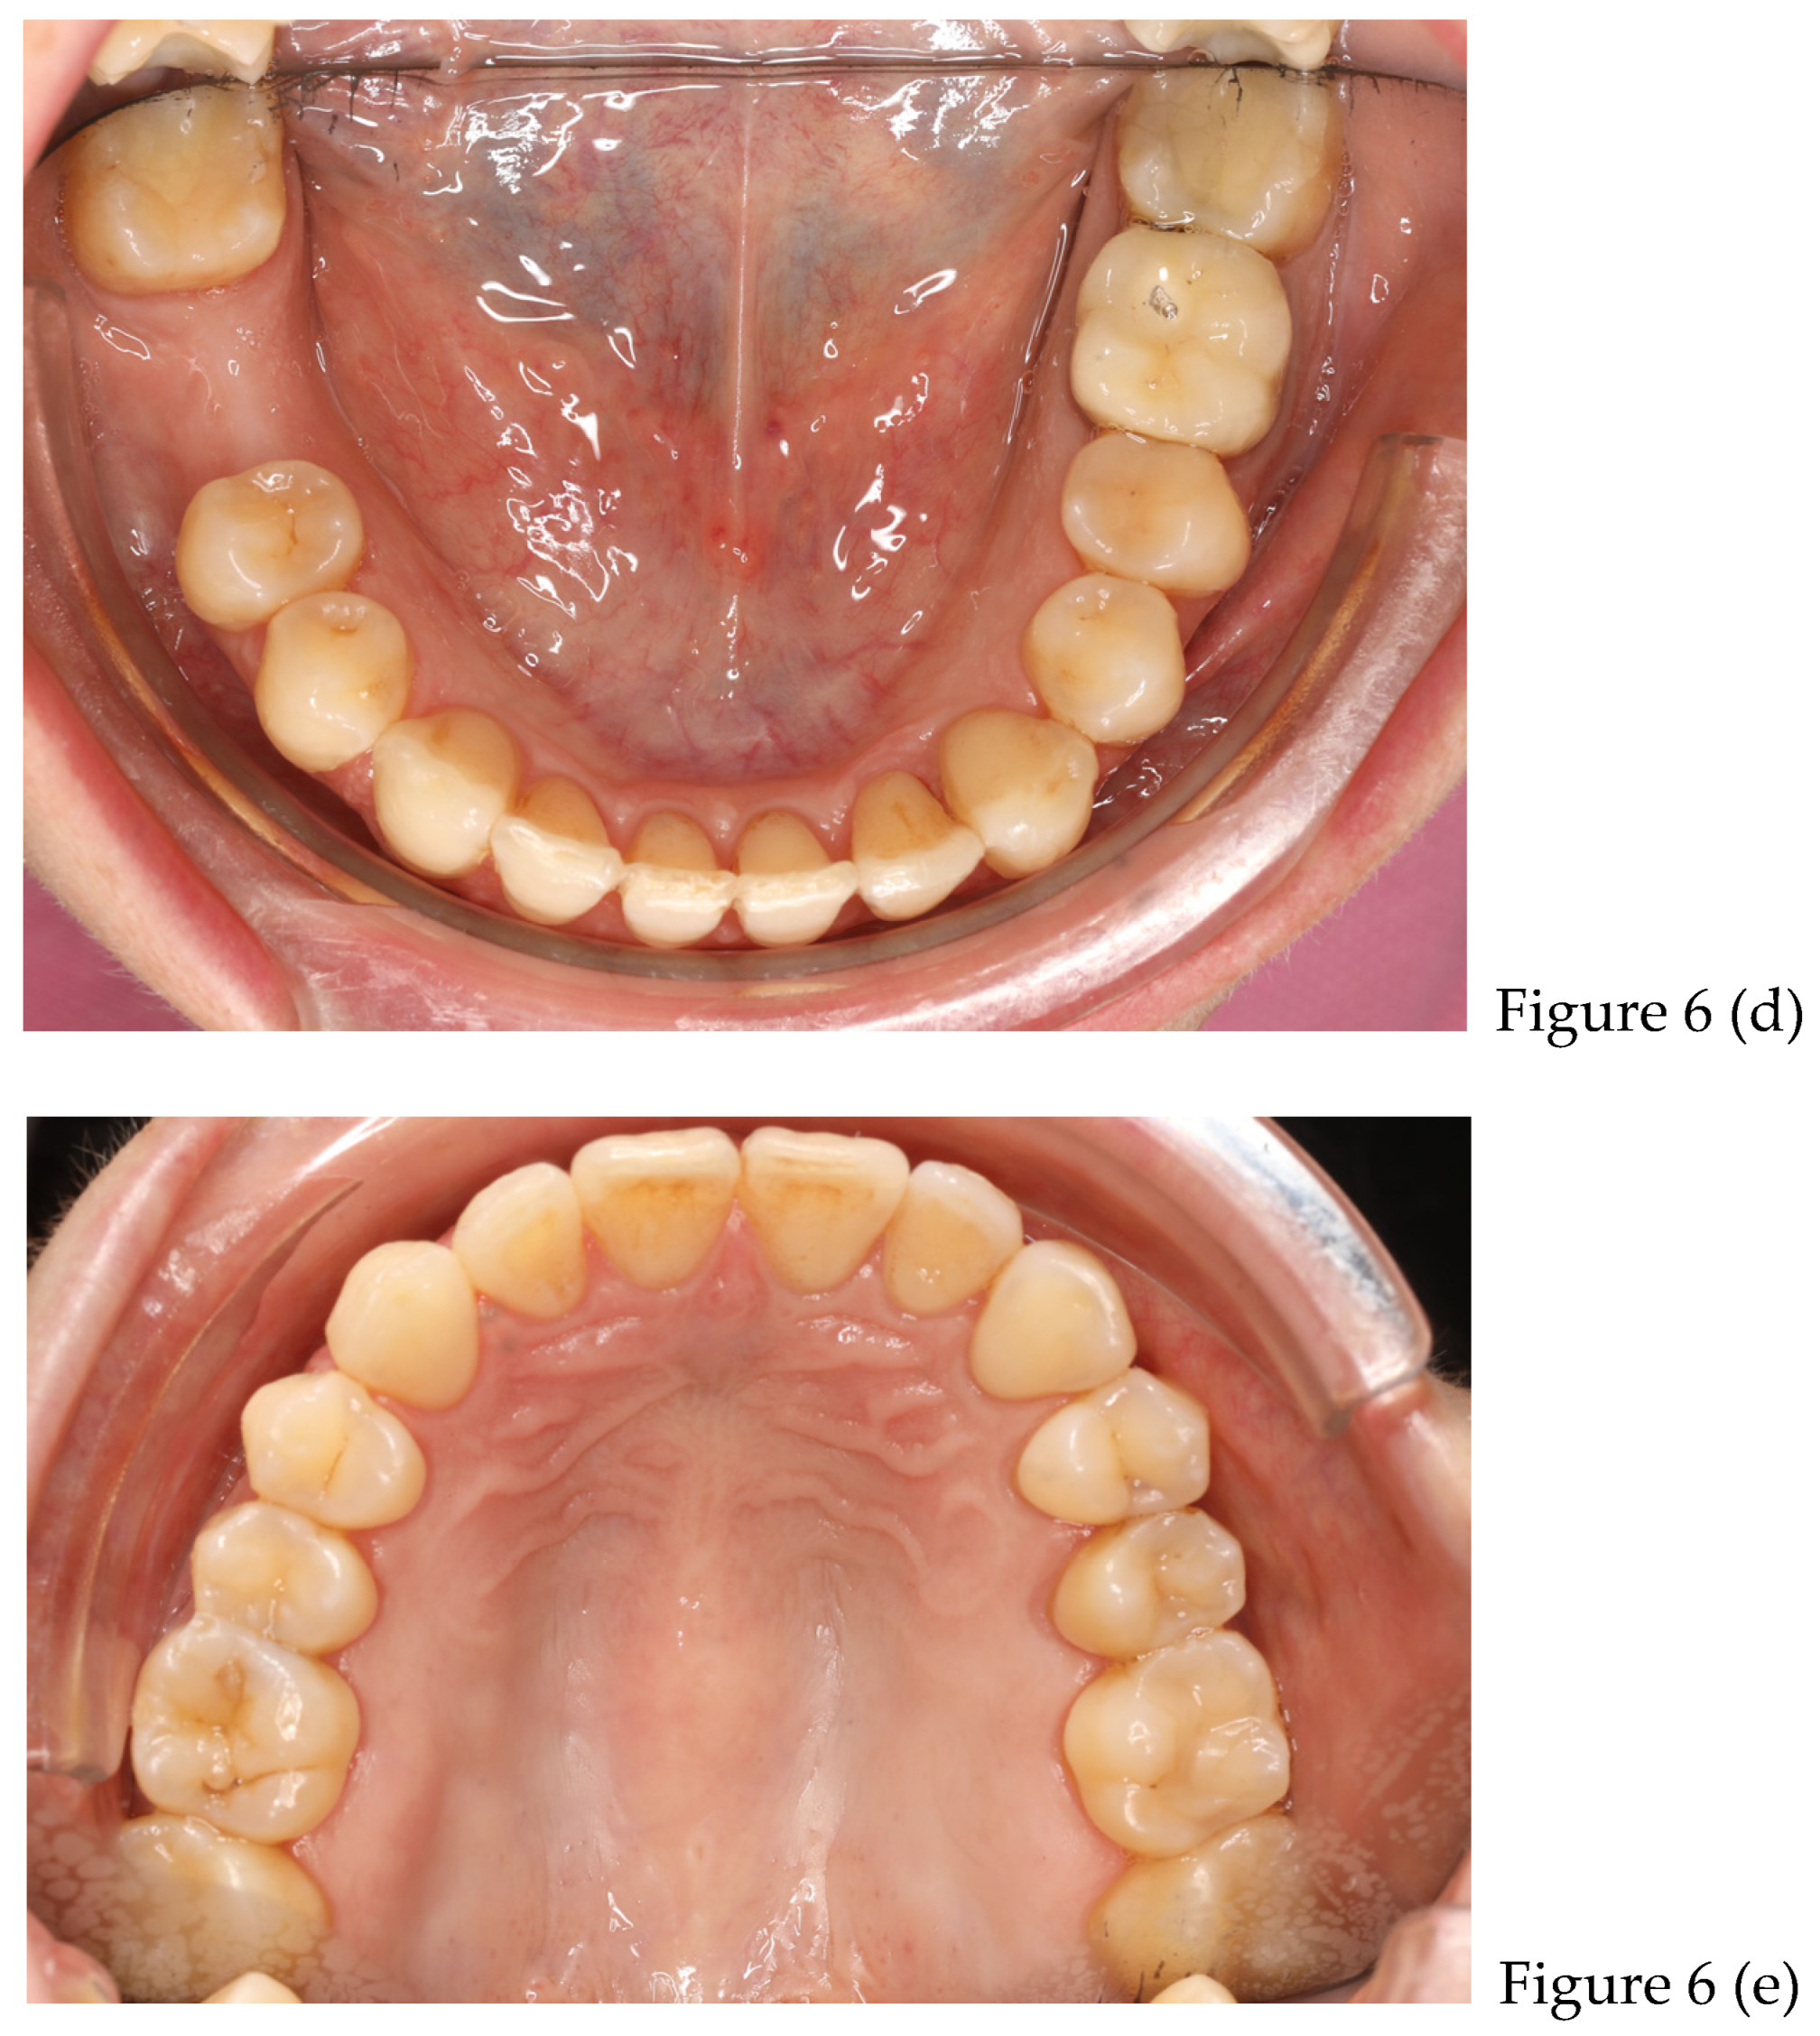

| preliminary photos | |

| after 8 months | Retainers + CBCT (t1) + final photos |